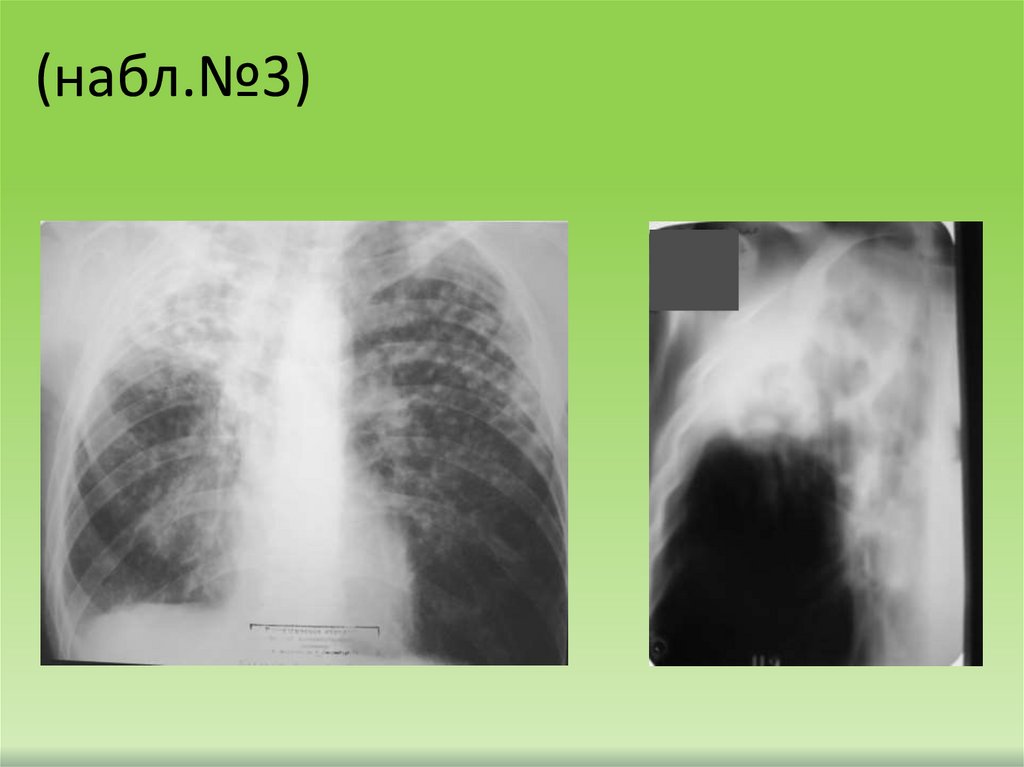

(набл.№3)